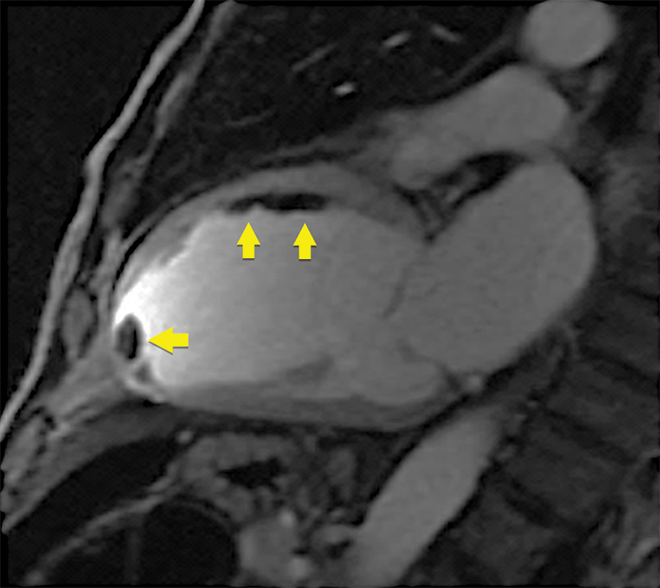

Box 3 – Early post-contrast cardiovascular magnetic resonance image showing multiple thrombi in the mid-anterior wall and left ventricular apex (arrows)

Note: on microsphere contrast echocardiography, only the apical thrombus was seen; the thrombi adherent to the mid-anterior wall were not observed.